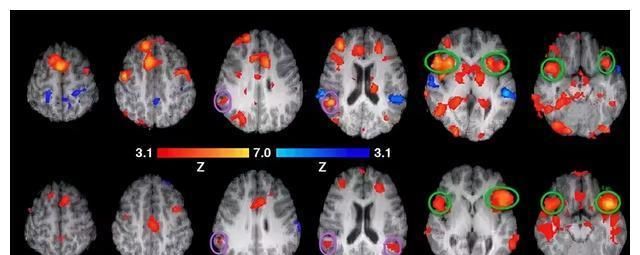

大脑扫描图像

台湾著名脑科学家洪兰在实验中发现,当盲人在摸读盲文点字时,他大脑中的视觉皮质会被触觉召唤过去用。如果把正常人的眼睛蒙住5天,他的视觉皮质就会开始改变,去做听觉、触觉方面的事。大脑的神经是“用进废退”的,常用的区块会因此增大,长久不用的地方会被挪作他用。

在美国一个实验中,研究者请大学生到实验室来学杂技团的抛球。练习前、练习三分钟后和三个月不碰球后都分别扫描一次大脑。当实验者把三张不同的大脑图摆在一起作比较的时候发现,第二张图的顶叶掌管空间运动的地方特别活化,血流量增多,区域变大。而持续三个月不练习抛球,那些地方又缩小了。而这些大学生早就过了青春期。